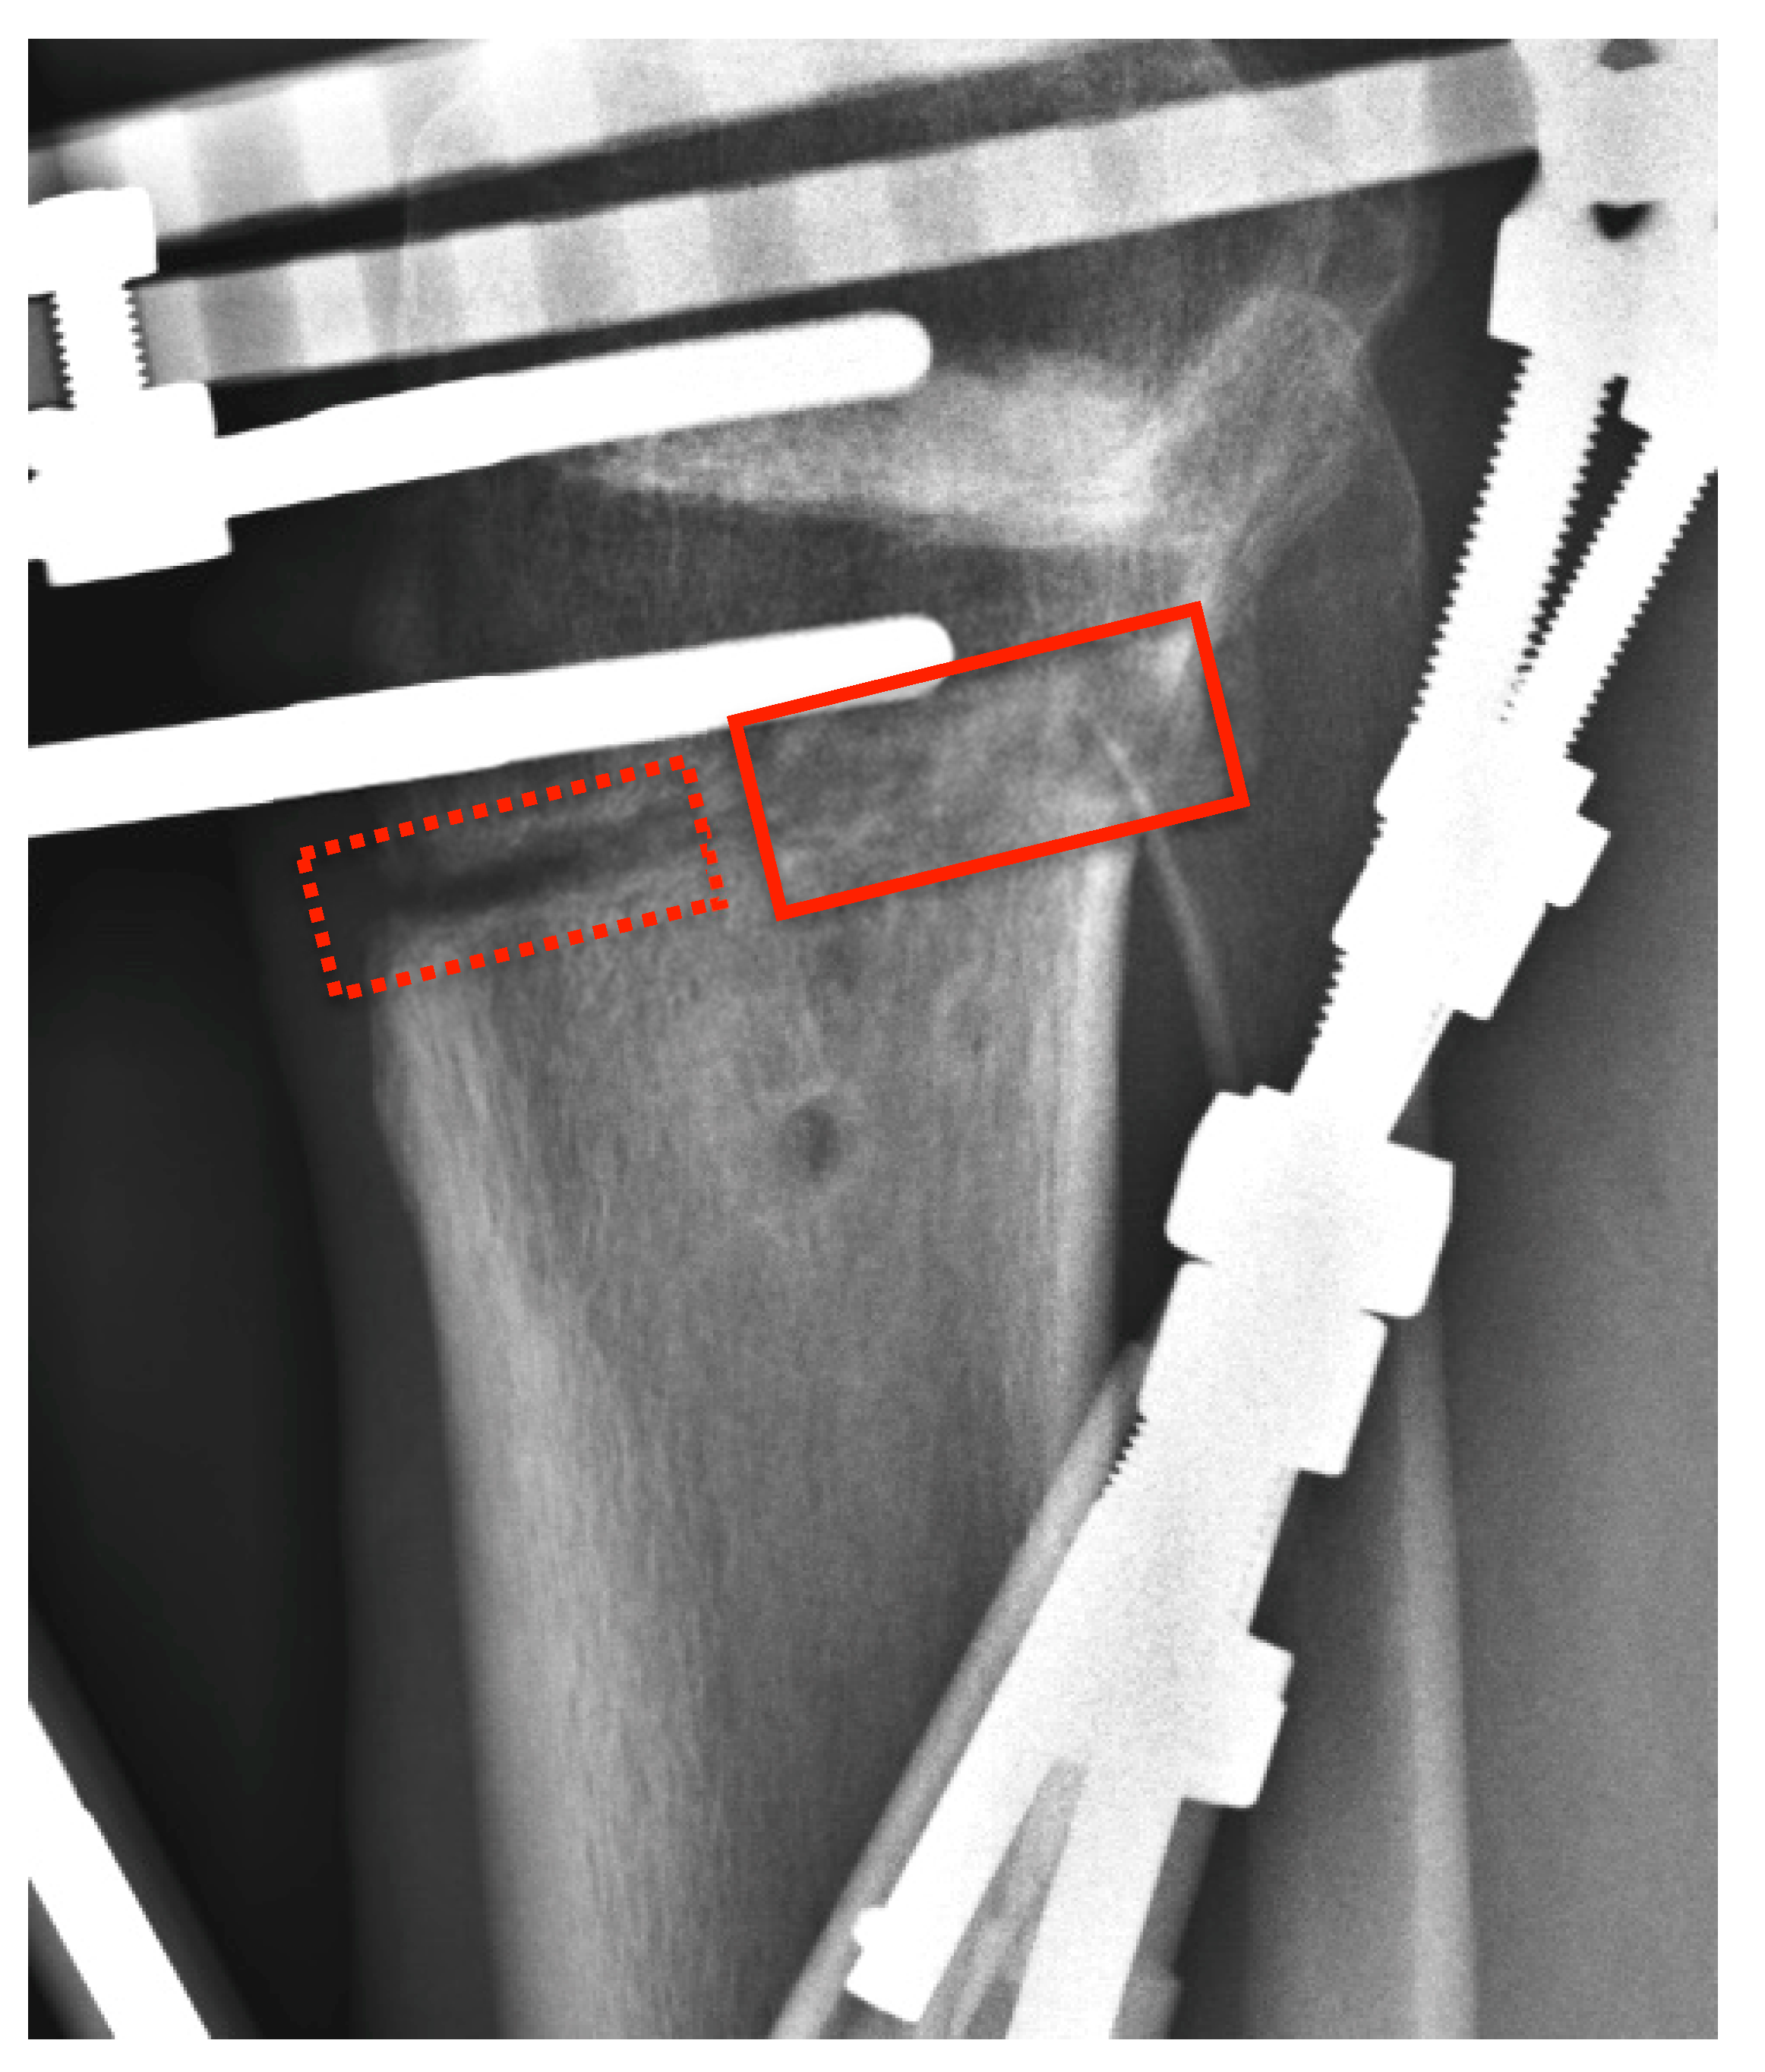

3.1. Clinical Results

3.2. Experimental Results